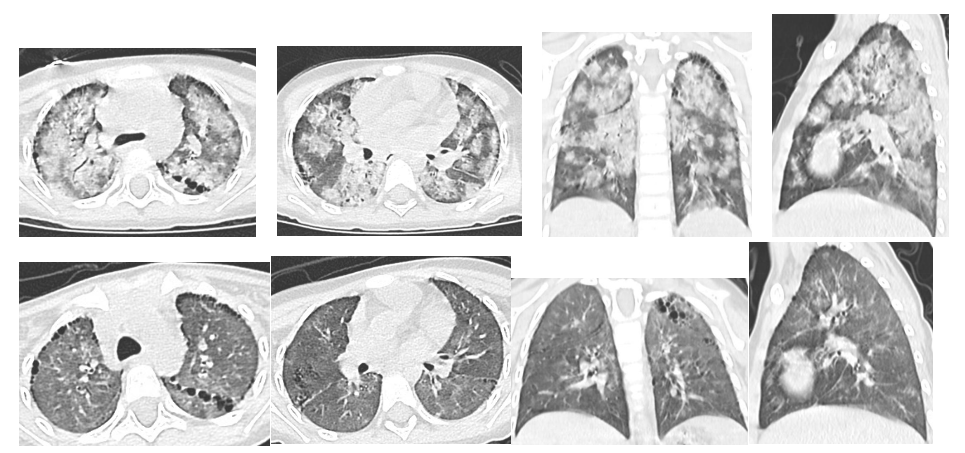

近日,长沙市妇幼保健院儿科急诊科接诊了一位4岁小女孩,她五官精致,却面如白纸,呼吸浅促,虚弱得没有力气说话。长沙市妇幼保健院儿科主任龚晓辉仔细查看患儿,发现她睑结膜、口唇、甲床均极度苍白,是典型的贫血貌。追问病史,家长说小朋友之前身体一直挺好的,就是最近这五天来,突然出现咳嗽、乏力,也不爱吃东西,脸色看着就不好了,就诊前两天更是粒米未进。情况十万火急,龚晓辉立即指挥抢救:紧急完善血常规、血型检查,交叉合血,准备为患儿输血,同时呼叫床旁彩超。超声结果很快出来:腹部、心脏均未见异常。没一会,医护人员就接到检验科危急值通知:血红蛋白仅21g/L!听到这个结果,在场所有人都紧张起来,这可是一个危及生命的数值。考虑过孩子存在严重贫血,但只有21g/L的血红蛋白还是让医生惊出一身汗,极重度贫血!情况太危急!龚主任再次分析病情:既往没有贫血情况,结合患儿年龄及平日饮食情况不支持营养性贫血;没有黄疸,酱油色尿,不支持溶血;没有肝脾淋巴结肿大等慢性贫血表现,没有皮肤粘膜出血,血小板不低,白血病等骨髓造血障碍也不支持,那就只有可能是失血了,而且存在急性失血!失血的部位到底在哪里呢?龚主任脑中划过一道亮光:听诊肺部是有湿啰音的,难道是肺泡出血?之前仅仅把它当作肺炎的表现了,必须马上完善肺部CT检查!影像结果弹出的一刹那,猜想得到了验证:真的是弥漫性肺泡出血。原来,血液是从肺部丢失了,考虑到“特发性肺含铁血黄素沉着症”可能性大,医护人员紧急联系病理科进行痰涂片检查,发现含铁血黄素细胞,支持了这一判断。在完善检查排除结核感染、血管炎、狼疮等各种感染及继发因素后,医护人员为患儿输血纠正贫血,使用糖皮质激素抑制免疫治疗。病情好转后,许继志主任给小朋友做了一次肺泡灌洗,灌洗液行普鲁士蓝染色,发现满屏的含铁血黄素细胞,特发性肺含铁血黄素沉着症确诊。